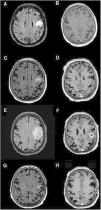

Brain MRI scan showing lesion progression. A-B) At admission. C-D) After 21 days of treatment. E-F) After 2 months of treatment. G-H) After 3 months of treatment. FLAIR (A, C, E, G) and gadolinium-enhanced T1-weighted sequences (B, D, F, H), axial plane. Images show the progression of a corticosubcortical lesion located in the left precentral gyrus/frontal operculum; the lesion is rounded and well defined, and appears iso- and hyperintense on FLAIR sequences (A, C, E, G) and hypointense on T1-weighted sequences (B, D, F, H), surrounded by vasogenic oedema and with contrast ring enhancement (B, D, F, H). Lesion size at admission was 15 × 12 mm (anteroposterior × lateromedial) (A). After a slight decrease in lesion size (12 × 7.5 mm) and significant improvements in the perilesional oedema (C), with contrast ring enhancement remaining nearly unchanged (D), remarkable increases were observed in lesion size (16 × 16 mm) and vasogenic oedema (E), as compared to the previous study (D). The lesion also changed in terms of morphology (more heterogeneous) (D), and displayed more extensive and irregular contrast uptake (F). Significant improvements were observed 3 months after onset of treatment with ibrutinib, with a decrease in lesion size and improvement in oedema (G); contrast uptake was barely perceptible (H). Changes were observed after craniotomy (biopsy) (G, H).

We present the case of a 56-year-old woman who consulted due to repeated episodes of transient dysarthria. She had history of arterial hypertension, dyslipidaemia, and chronic kidney disease. She had undergone kidney transplantation and had been receiving immunosuppressive therapy since 1981; at the time of consultation, she was receiving prednisone (5 mg/24 h), tacrolimus (2 mg/24 h), and mycophenolate mofetil (360 mg/12 h). An emergency CT scan revealed a hypodense lesion in the left frontal lobe. During hospitalisation, she presented episodes of anarthria and clonic movements affecting the perioral region, suggestive of opercular epilepsy, and started treatment with levetiracetam dosed at 500 mg/12 hours. Graft failure was also observed, and haemodialysis was restarted. A brain MRI scan (Fig. 1) revealed a corticosubcortical lesion in the left frontal lobe, vasogenic oedema, and ring contrast enhancement; differential diagnosis between infectious and neoplastic processes was considered. Empirical antibiotic therapy was started and immunosuppressive therapy suspended. Whole-body CT and PET/CT scans revealed no abnormalities. CSF biochemical analysis yielded normal results, with negative results for immunophenotyping, cytology, and microbiology studies (cryptococcal antigen screening; venereal disease research laboratory test; polymerase chain reaction assay for Toxoplasma gondii, Listeria monocytogenes, and John Cunningham virus; fungal and mycobacterial cultures). The patient remained asymptomatic after starting antiepileptic treatment. Radiological improvements were observed after 21 days of antibiotic therapy (Fig. 1). Two months later, she presented progressive speech impairment with naming difficulties, right facial paresis, and right faciobrachial clonic movements, which were controlled with levetiracetam (1000 mg/12 h) and lacosamide (50 mg/12 h). An MRI scan revealed increased lesion size and oedema extension. Results from a brain biopsy (Fig. 2) revealed grade 3 lymphomatoid granulomatosis. Additional whole-body CT and PET/CT scans were performed to detect any metastasis, yielding normal results. After a multidisciplinary assessment, radiation therapy and chemotherapy (R-CHOP, rituximab) were ruled out due to the patient’s poor health status and history of chronic kidney disease. Treatment was started with ibrutinib (a Bruton’s tyrosine kinase inhibitor) at 560 mg/day for compassionate use; tolerance was good. After 8 months of treatment, the patient presented a partial clinical improvement (mild anomia and facial paresis) and significant radiological improvement (Fig. 1).